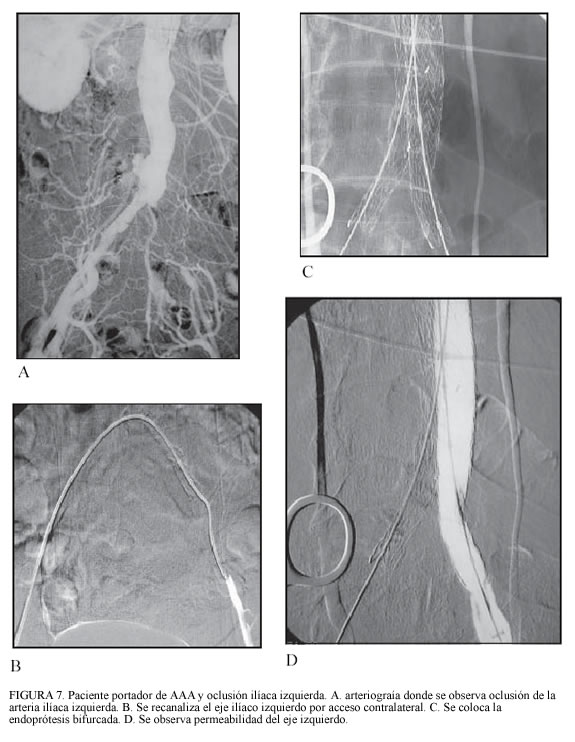

Situación similar ocurre cuando existe una rotura contenida en pacientes de alto riesgo por sus comorbilidades. En esta situación se plantea el no hacer nada en caso que el enfermo sobreviva, pero es difícil que los familiares decidan llevárselo del hospital en estas circunstancias, por lo que debe valorarse la corrección de la rotura (figura 1).

Cuando existen casos de ruptura, las posibilidades de supervivencia ya han sido comentadas con anterioridad, lo que demuestra que llegando al hospital el índice de mortalidad es menor; pero si además se aplica cirugía endovascular, las probabilidades de supervivencia de un AAA roto aumentan considerablemente.

La reparación endovascular de AAA de aneurismas rotos es posible. Veith y su grupo de Montefiore han publicado su experiencia con 36 pacientes con anatomía favorable, con reanimación hipotensiva y utilización selectiva de balón de oclusión en la aorta proximal, siendo posible en 30 de 36, mortalidad operatoria 4 pacientes (11%), lo cual lo convierte en una alternativa en pacientes con AAA roto (18, 19).